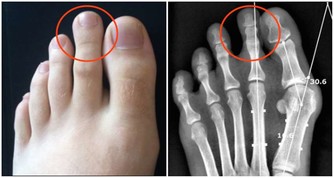

2016年汪清查出懷孕,家人喜出望外。然而當她去醫院做孕檢時卻引發了一場“地震”——她被查出患有梅毒,而先生沒有被感染。

婆婆和先生懷疑的眼光,讓她幾乎崩潰。醫生仔細詢問,她才回憶起自己結婚前,曾在路邊小攤上打過耳洞。“很可能就是那次埋下禍根。”